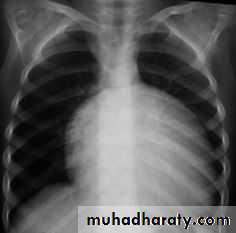

T.G.A represents about 5% of congenital heart defects, and it is the most common cyanotic lesion to present in the Newborn period . T.G.A is ventriculoarterial discordance secondary to abnormalities of septation of the truncus arteriosus, the aorta arises from the right ventricle, anterior and to the right of the pulmonary artery, which arises from the left

History of cyanosis from birth is always present.

Moderate to severe cyanosis and tachypnea.